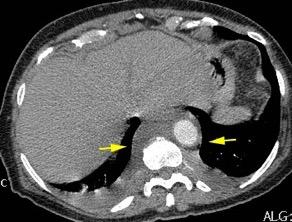

T. mixto de células

Ganglios retroperitoneales (flechas negras)

germinales del testículo izquierdo Nódulos pulmonares múltiples. (flechas verdes). Ganglios paratraqueales. (flechas amarillas). Dudoso ensanchamiento retrocrural (flechas negras)

Panda A et al. “Straddling Across Boundaries”. Thoracoabdominal Lesions: Spectrum and Pattern Approach. Curr Probl Diagn Radiol, 2015